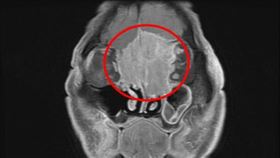

他誤以為針眼醫一看:癌細胞已侵蝕鼻樑骨

79歲的黃先生近2年常覺得眼睛不舒服,原以為是針眼做...